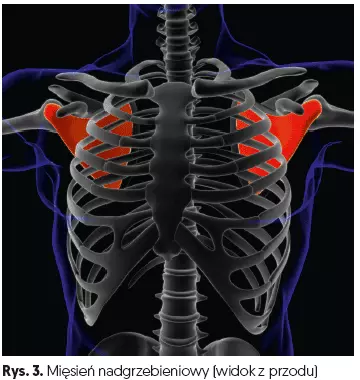

Obszar pomiędzy głową kości ramiennej a wyrostkiem barkowym jest nazywany przestrzenią podbarkową. W tej przestrzeni znajdują się: ścięgno mięśnia nadgrzebieniowego (jeden z mięśni stożka rotatorów), długa głowa ścięgna mięśnia dwugłowego ramienia, kaletka podbarkowa i torebka stawu barkowego.